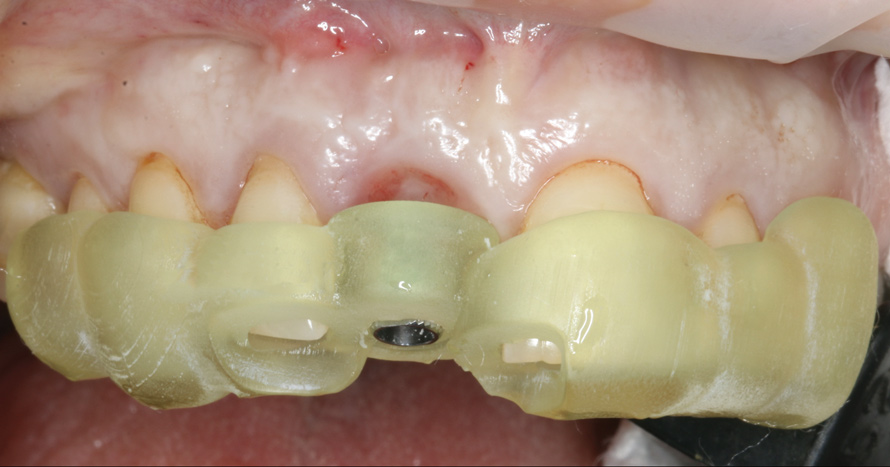

The patient was postoperatively evaluated at 1-, 2-, 4-, 8-, and 12-week recall appointments. The sutures were removed at the 2-week appointment, and the patient was instructed to rinse twice daily and avoid brushing the anterior maxilla. Prior to provisionalization of the implant, the site was allowed to heal for 6 months, during which time the patient was temporized with another Maryland bridge. At the 6-month recall appointment, full mouth periodontal maintenance was completed, and an implant-retained acrylic provisional restoration was placed (Figure 23 through Figure 25). An acrylic provisional restoration allows for soft-tissue attachment while preventing apical migration of the gingival margin. After a 3-month provisionalization period, the final prosthesis was delivered (Figure 26 through Figure 29), and the patient was scheduled for ongoing 3-month recall appointments for periodontal maintenance.

23. Facial view, distal view, and radiograph of the acrylic implant-retained provisional restoration placed at the implant uncovering surgery to contour the soft-tissue profile for final restoration. Critical and subcritical contours follow the anatomic crown profile as seen in both the mesiodistal and buccolingual dimensions.

Figure 23

(24.) Facial view, distal view, and radiograph of the acrylic implant-retained provisional restoration placed at the implant uncovering surgery to contour the soft-tissue profile for final restoration. Critical and subcritical contours follow the anatomic crown profile as seen in both the mesiodistal and buccolingual dimensions.

Figure 24

(25.) Facial view, distal view, and radiograph of the acrylic implant-retained provisional restoration placed at the implant uncovering surgery to contour the soft-tissue profile for final restoration. Critical and subcritical contours follow the anatomic crown profile as seen in both the mesiodistal and buccolingual dimensions.

Figure 25